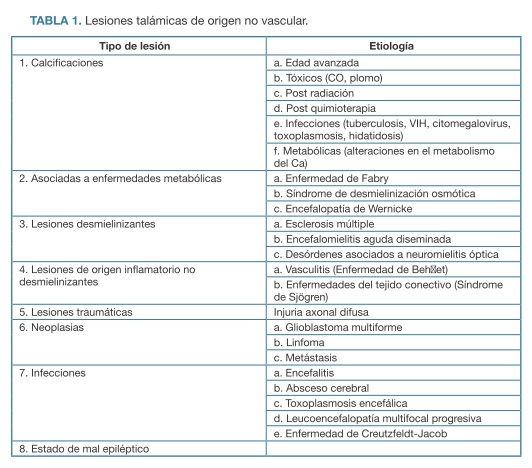

Existen también, en menor proporción, lesiones de origen no vascular (Tabla 1). (7)